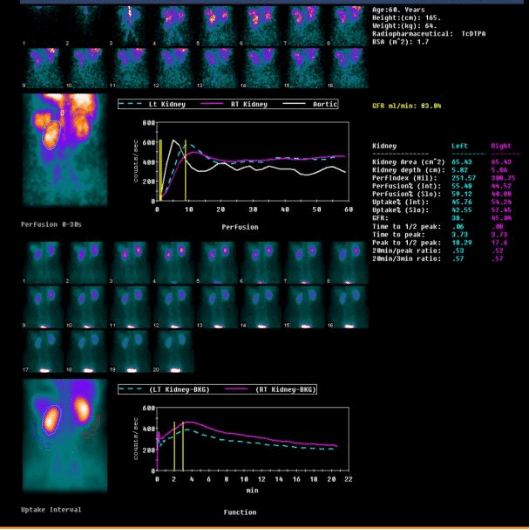

2、肾动脉狭窄患者评估患肾功能

左图,男,57岁,右肾动脉狭窄,右肾功能正常。

右图,男,51岁,右肾动脉狭窄,导致右肾功能受损(右侧GFR 15)。

以上三组病例告诉我们,相同的疾病,对肾脏的影响可能不同,肾动态显像可以帮助我们定量的判断两个肾脏分别的功能。